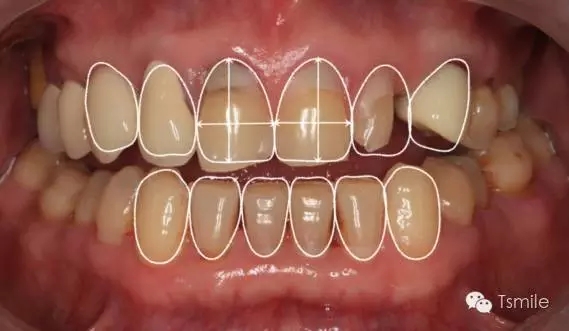

在前牙的美學(xué)分析中有四個最重要的美學(xué)影響因素,稱之為前牙美學(xué)四要素。包括上中切牙切緣的位置、上中切牙臨床冠的寬長比、上中切牙齦緣的位置、上前牙的寬度比例。這四要素是影響前牙美學(xué)的主要因素,根據(jù)這四要素就可以簡單、快速、準(zhǔn)確地分析患者前牙存在的美學(xué)缺陷。根據(jù)這四因素就可以準(zhǔn)確、直接地進(jìn)行患者前牙的美學(xué)修復(fù)設(shè)計。

例如面對一個牙列重度磨耗的美學(xué)修復(fù)患者,我們首先根據(jù)患者主訴和美學(xué)檢查形成美學(xué)設(shè)計,然后通過數(shù)碼圖像表達(dá)美學(xué)設(shè)計思想,制作診斷蠟型,口內(nèi)制作診斷飾面,更加真實地表達(dá)美學(xué)設(shè)計。根據(jù)患者的要求和口內(nèi)試戴情況調(diào)改診斷飾面,最終確定美學(xué)修復(fù)設(shè)計,即最終修復(fù)體的各種美學(xué)參數(shù)。接下來就是美學(xué)實現(xiàn)過程,在診斷飾面上進(jìn)行精確地牙體預(yù)備,制取印模和工作模型,技師按照最終診斷飾面的形態(tài)、大小和排列制作最終美學(xué)修復(fù)體,最后完成修復(fù)體粘接。